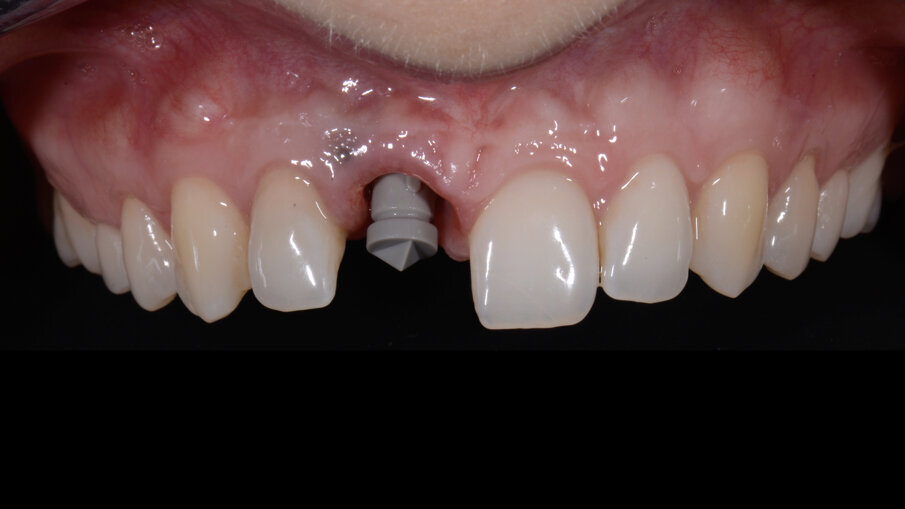

In seguito ad un riassorbimento radicolare esterno, una giovane paziente di 28 anni danneggia irreversibilmente il dente 1.1. È presente una fistola vestibolare e la sequenza radiografica mostrava un progressivo danno a carico della radice con coinvolgimento del tronco radicolare e del terzo cervicale del dente (Figg. 2-5).

Figg. 2-4_Immagini iniziali.

Fig. 27_Il provvisorio nella seduta chirurgica viene avvitato immediatamente all’impianto.